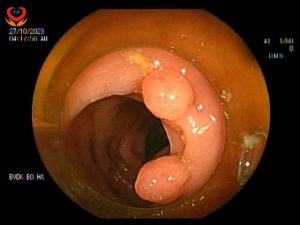

NỘI SOI ĐẠI TRÀNG PHÁT HIỆN HƠN 10 POLYP

Trong quá trình nội soi, bác sĩ đã phát hiện hơn 10 polyp nằm rải rác ở đại tràng, nguy hiểm hơn một số polyp đang có hiện tượng xung huyết gây ra đau đớn cho bệnh nhân.

Bác sĩ Đỗ Trọng Đức cùng các điều dưỡng, với kinh nghiệm cũng như sự hỗ trợ của hệ thống nội soi hiện đại, đã tiến hành cắt toàn bộ polyp ở vị trí đại tràng.